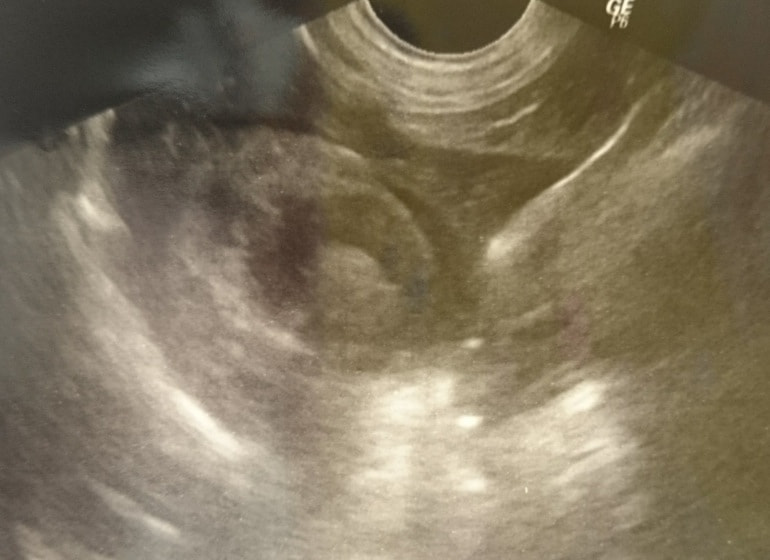

エコー検査にて腹水貯留を認め、エコーガイド下で穿刺を行い腹水が尿であることを確認しました。

■ 症例 雑種猫 1歳 去勢雄

トイレにいる時間が長く、1回の排尿量が少ないとの主訴で来院。エコー検査にて、膀胱内に多量の微細砂粒を認めました。また、カテーテルが尿道の途中から入っていかず、砂粒が原因による尿道閉塞を起こしていることが確認されました。カテーテルから生理食塩水を注入することにより、詰まった砂粒を膀胱内に押し戻し、一時的に尿道閉塞を解除、尿検査の結果、微細砂粒はストルバイトと診断しました。食事療法および膀胱炎に対する対症療法を開始しましたが、連日尿道閉塞を繰り返すことから、会陰尿道瘻術を実施しました。術後は尿道閉塞の再発は無く、食事療法の継続で経過は順調です。